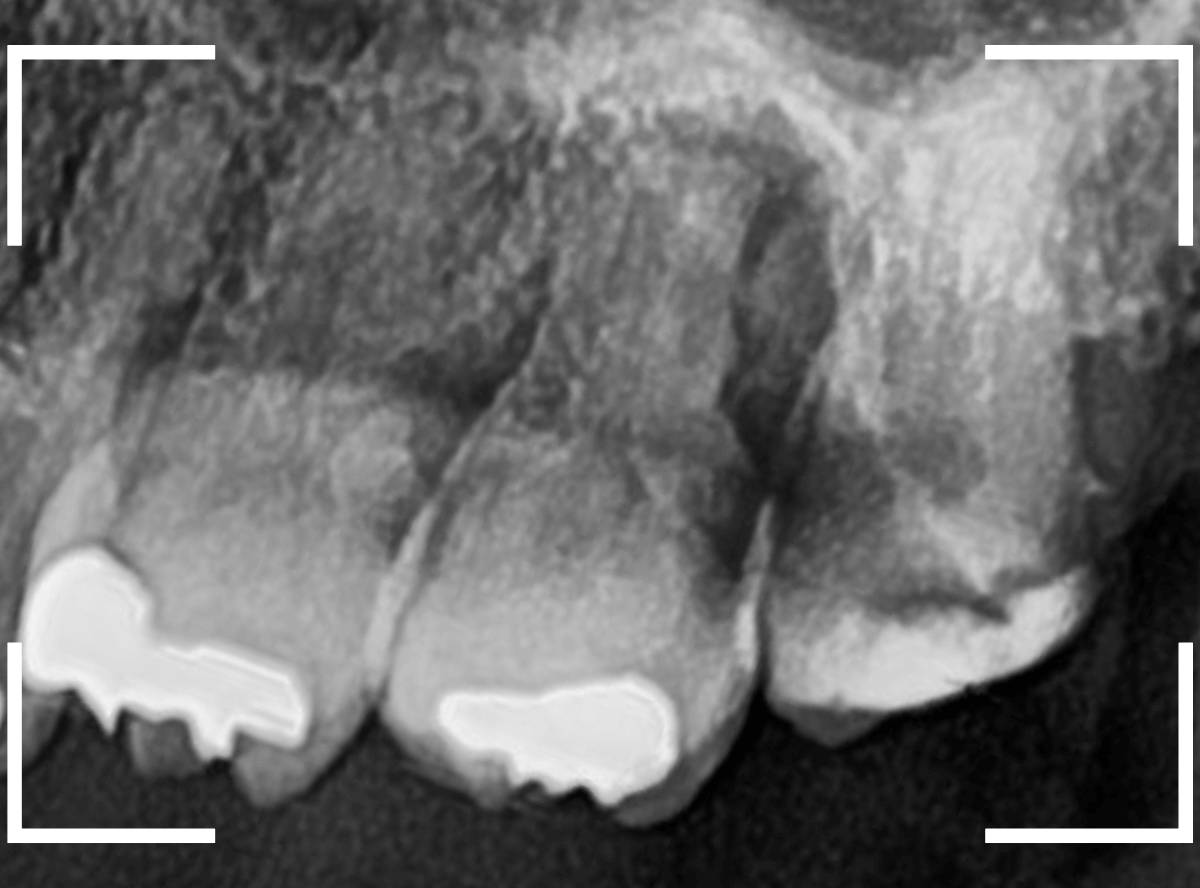

レントゲン写真です。

レジンの下が虫歯になっているのがわかります。

レントゲン写真で確認します。

青い線が歯の神経、赤い線が虫歯です。

おやしらずがあった際にはわかりづらかったですが、歯の後ろ側のおやしらずが重なっていたところが虫歯になっているのがわかります。

おやしらずが原因で、このように手前の歯が虫歯になってしまう事が多いために、抜歯を勧められる事が多いのです。

そして、虫歯の部分におやしらずが被さっていたために、しみる症状などを感じなかったのです。